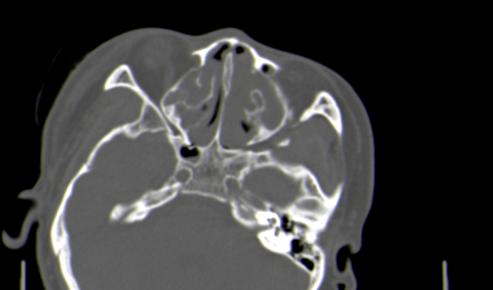

以下是引用皎皎白驹在2006-11-29 8:48:00的发言:[br]影像表现:双侧筛窦和上颌窦、鼻腔内均密度增高,右侧视神经增粗、弯曲,左筛窦顶部筛板及右侧纸板近视神经孔区可见骨折线。[br]结合临床表现考虑:右侧筛窦纸板近视神经孔区骨折致右侧视神经损伤。最好做个眼眶冠状扫描,更明确右侧视神经管是否狭窄。

以下是引用w_jianhua在2006-11-29 10:07:00的发言:[br]影像表现:双侧筛窦和上颌窦、鼻腔内均密度增高,右侧视神经增粗、弯曲,左筛窦顶部筛板及右侧纸板近视神经孔区可见骨折线。[br]结合临床表现考虑:右侧筛窦纸板近视神经孔区骨折致右侧视神经损伤。最好做个眼眶冠状扫描,更明确右侧视神经管是否狭窄。 [br] [br]支持[br]

以下是引用守望可可西里在2006-11-29 9:46:00的发言:[br][quote]以下是引用皎皎白驹在2006-11-29 8:48:00的发言:[br]影像表现:双侧筛窦和上颌窦、鼻腔内均密度增高,右侧视神经增粗、弯曲,左筛窦顶部筛板及右侧纸板近视神经孔区可见骨折线。[br]结合临床表现考虑:右侧筛窦纸板近视神经孔区骨折致右侧视神经损伤。最好做个眼眶冠状扫描,更明确右侧视神经管是否狭窄。